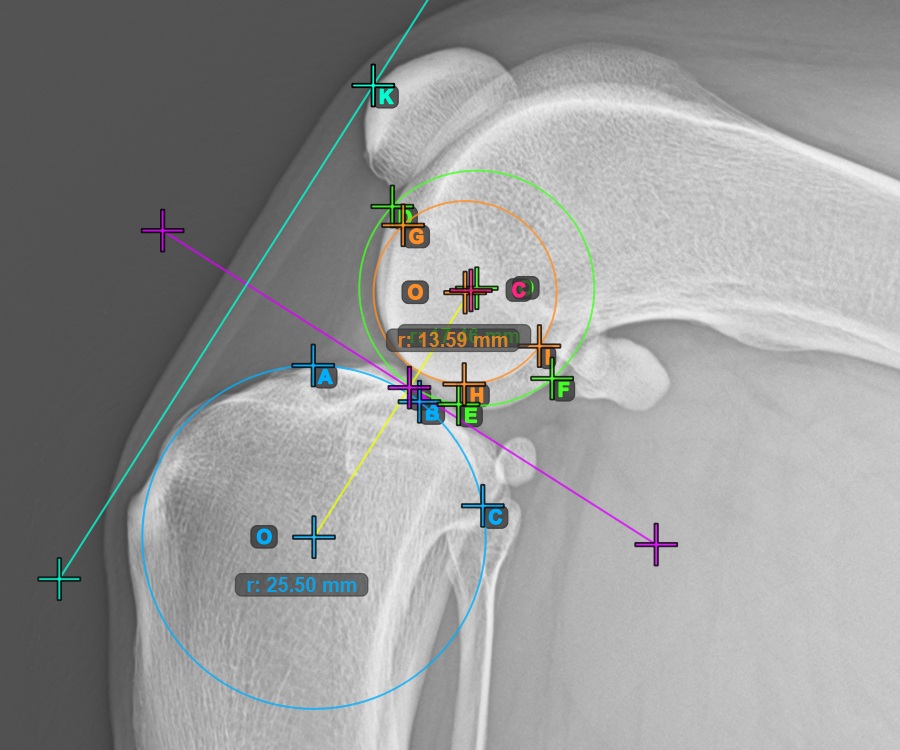

Additionally, mark the three points on the articular surface of the second Condylus Femoris.

Mark the three points on the inner (secondary) condylus of the femoral bone (Condylus Femoris). Regardless of the order, make sure to mark the most cranial point, the most caudal point and the midpoint of the Condylus Femoris. A circle will be automatically constructed based on the three placed points.

The image below represents a typical placement of the three points on the second Condylus Femoris.